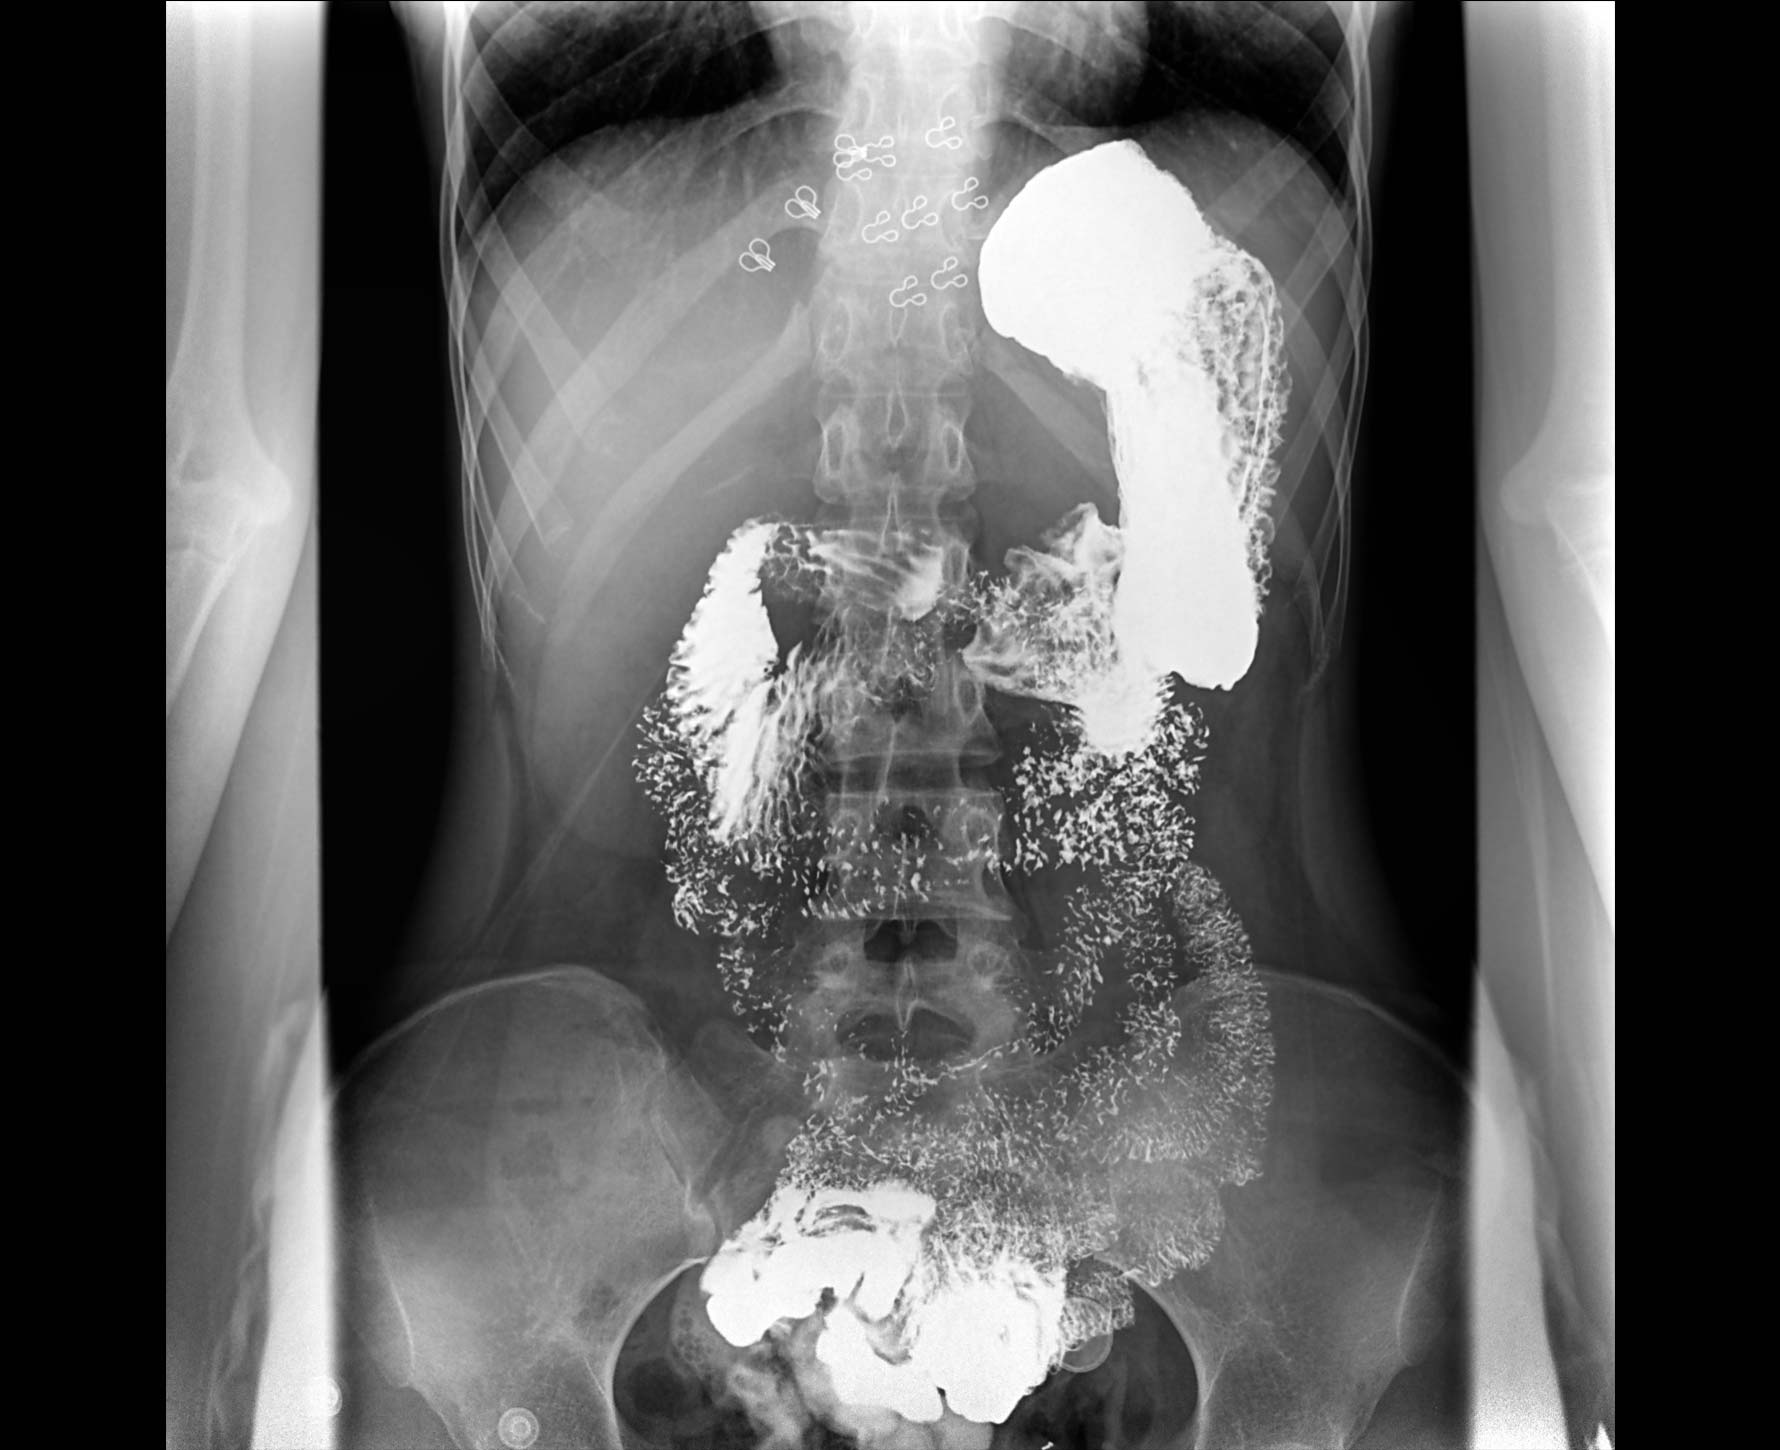

• 造影

适用于各种普通

及特殊胃肠造影检查

对胃肠造影检查影像实时保存,多次回放以便确定病灶部位,患者确诊好帮手,减少漏诊。

临床图像